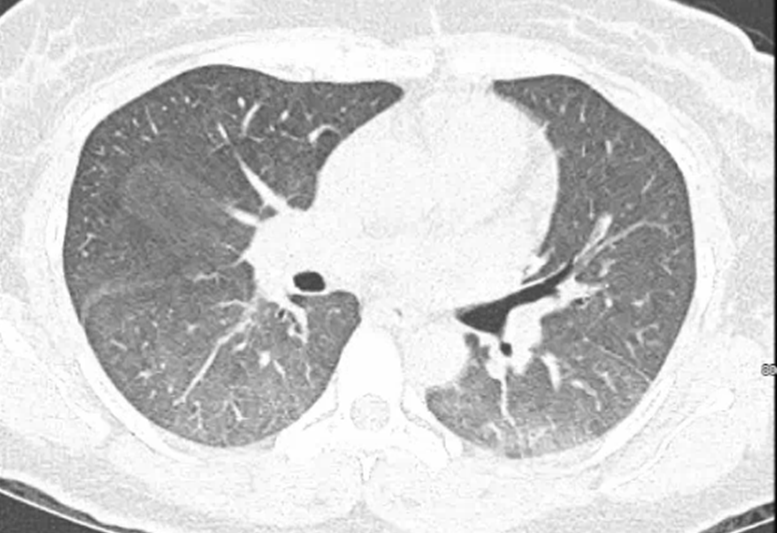

Be aware of rapidly progressive ILD in pts w/high titer MDA5+ &⬆️ferritin. This patient had a clear CXR, but CT showed GGO. The patient decompensated w/in weeks. 2023 ACR guidelines for ILD Rx: assets.contentstack.io/v3/assets/blte…

#dermatomyositis #RheumDermGR @JetPattersonMD @BrookeS_Mills